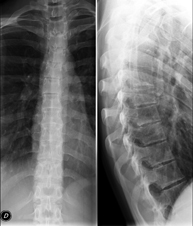

- Thoracic spine X-ray

This technique uses X-ray rendered imaging for examining the thoracic spine. Indicated for: trauma, pain, scoliosis.

This technique uses X-ray rendered imaging to examine the thoracic spine. Indicated for: trauma, back pain.